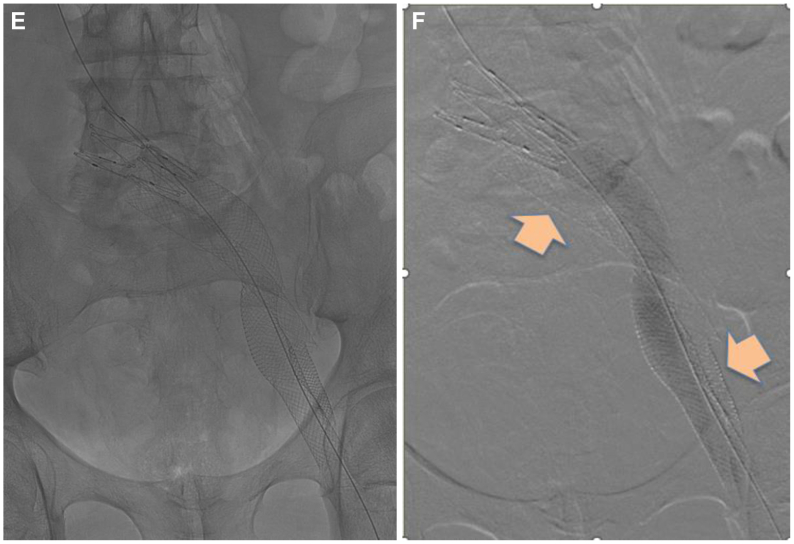

Fig 3.

(A) Initial venogram demonstrating an occluded iliofemoral venous stent; (B) Successful wire recanalization around the pre-existing stent; (C) Intravascular ultrasound (IVUS) confirmation of entry into caudal inferior vena cava; (D) Sequential angioplasty of endobypass tract; (E) Fluoroscopic image depicting the configuration of the original stent and the new conduit around it. (F) Completion venogram depicting a patent endobypass conduit of Wallstent-Z stent combination with orange arrow depicting the occluded original stent column.